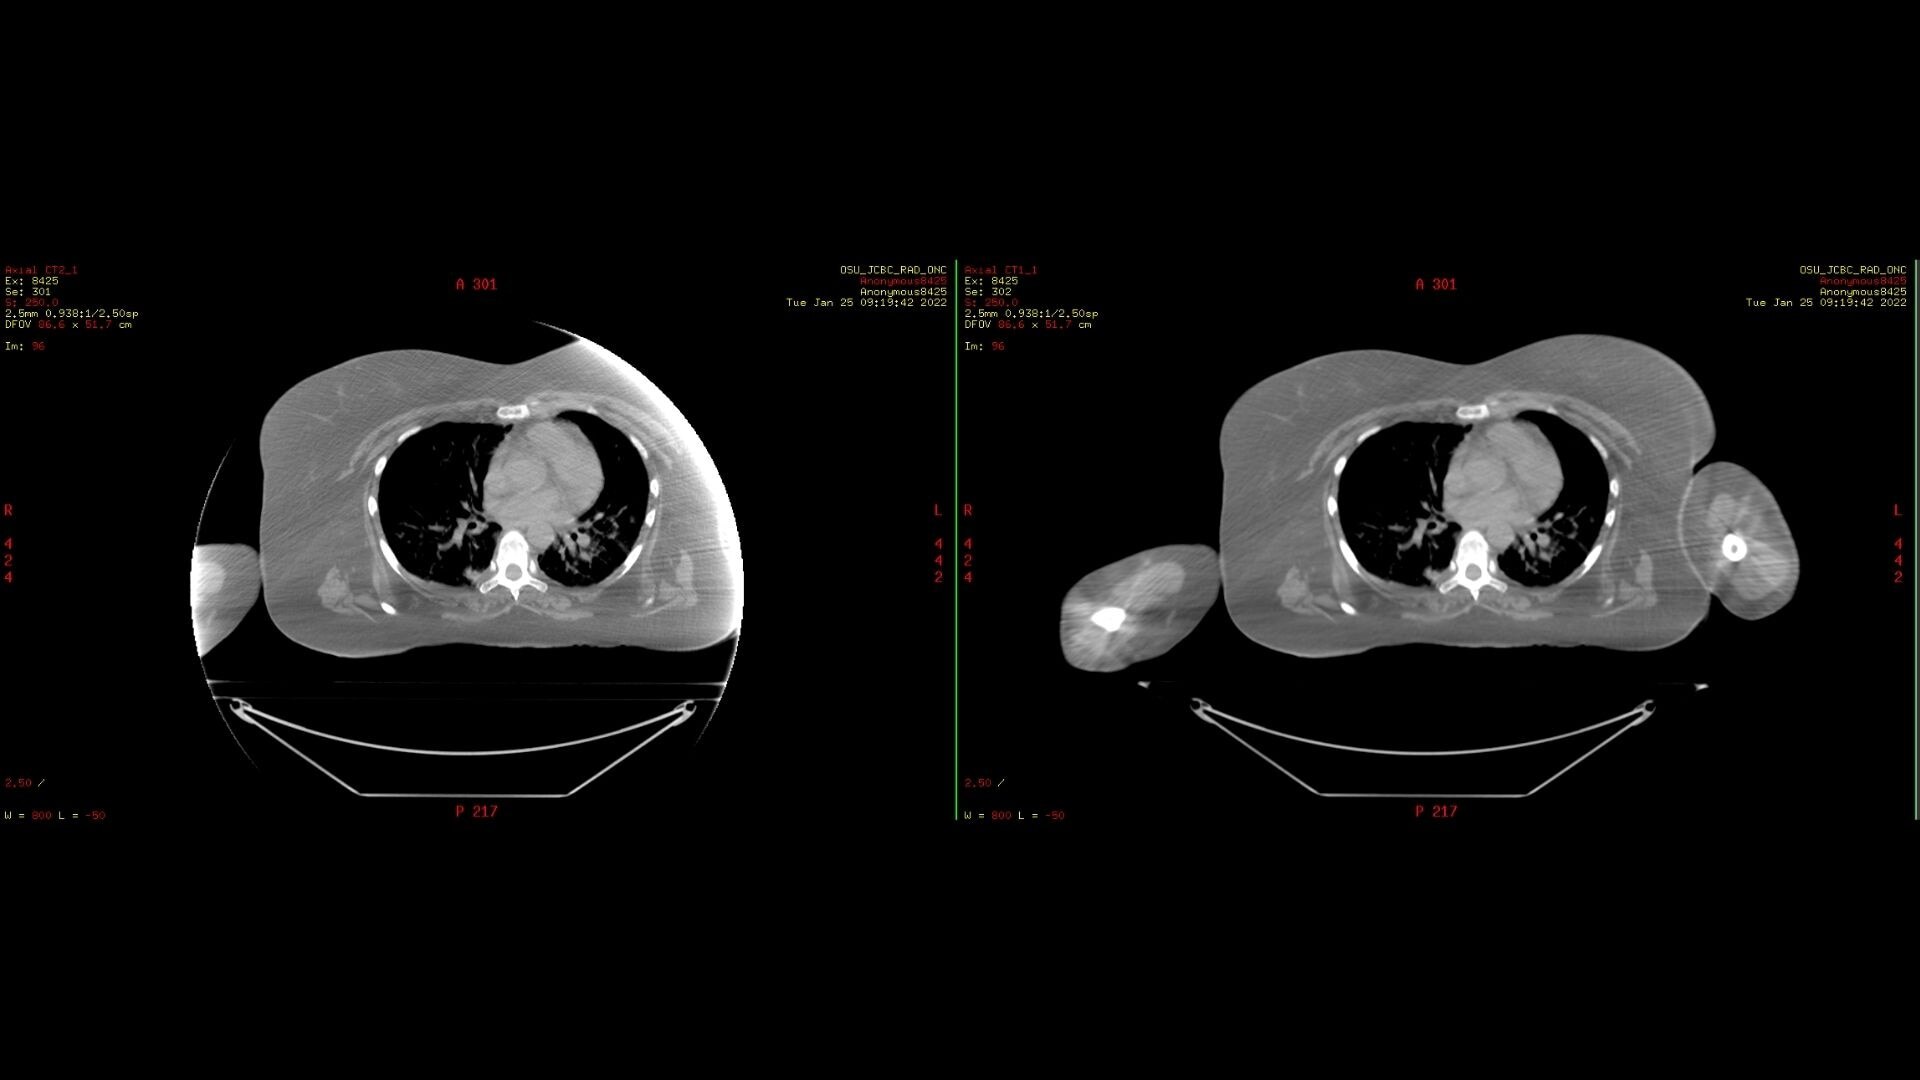

Smart MAR 2.0

Smart MAR 2.0 is designed to reduce artifacts of high-density materials, including orthopedic implants, dental fillings, and other metal in the body. Our metal artifact correction technology is based on raw data, enabling you to reduce artifacts caused by both photon starvation and beam hardening, revealing the anatomy that was concealed all the way out to the edge of the bore.